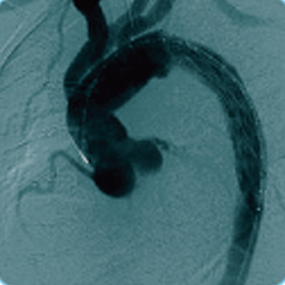

CRONUS®/通天刀™术中支架系统

CRONUS®/通天刀™术中支架用于 DeBakeyⅠ型主动脉夹层的手术治疗和部分 DeBakey Ⅲ 型主动脉夹层的手术治疗。